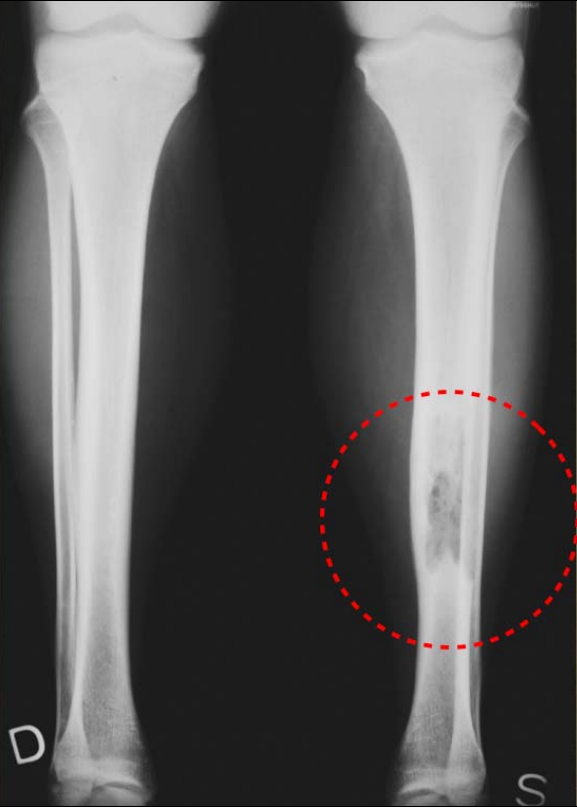

Figure4